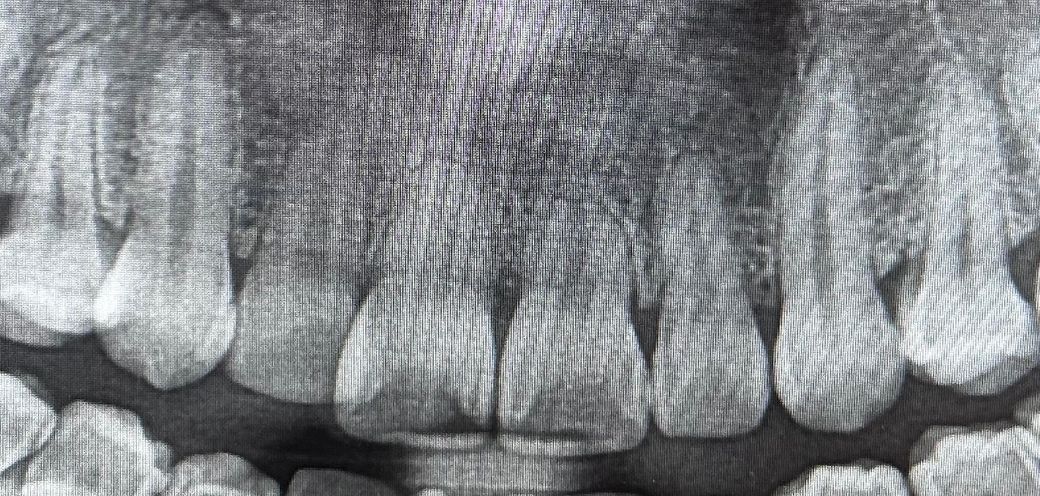

치근이 짧은 경우 치아교정 어떤게 더 좋을까요?

치근이 짧은데 덧니때문에 교정을 하고싶습니다.

앞니 치근이 짧아서 더 흡수가 될까봐 걱정입니다. 왜 치근이 짧아졌는지는 모르겠어요. 원래 짧은건지 나쁜 버릇때문인지, 앞니를 부딪히거나 그런 사고는 기억이 안납니다.

• 1번 째 사진